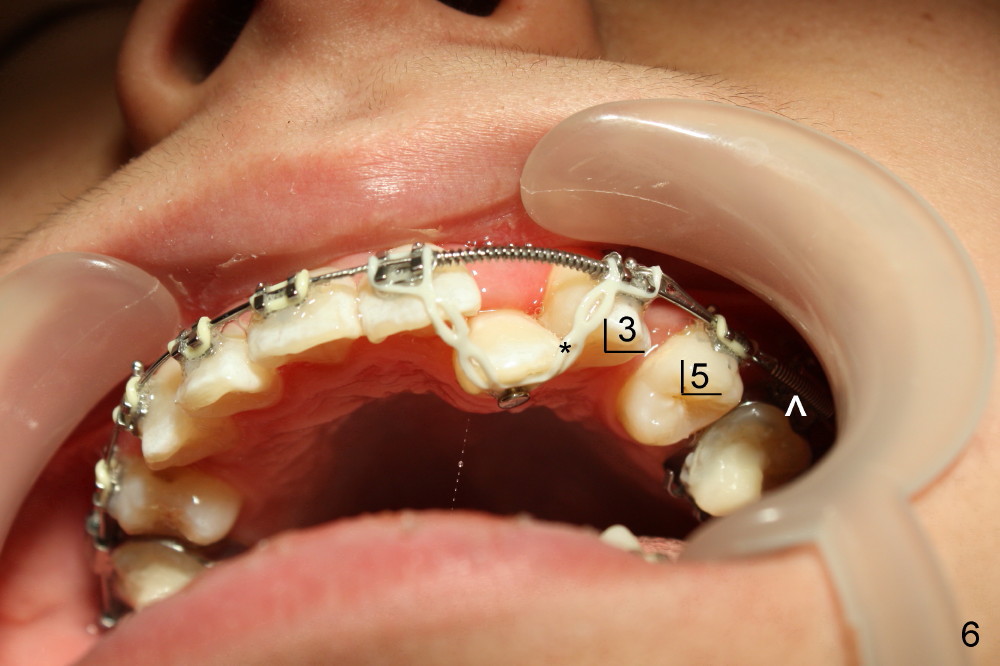

Five weeks later, .018 ss wires are installed with open coil spring between UL 1 and 3 and power chain between UL 3 and 7 (Fig.4). Three months post-bracketing, space is being created for UL 2 (Fig.5). Four months post-bracketing, a lingual button is placed on UL2 with power chain x7 (Fig.6: sling shot); Pletcher's spring between UL 3 and 7 (^).